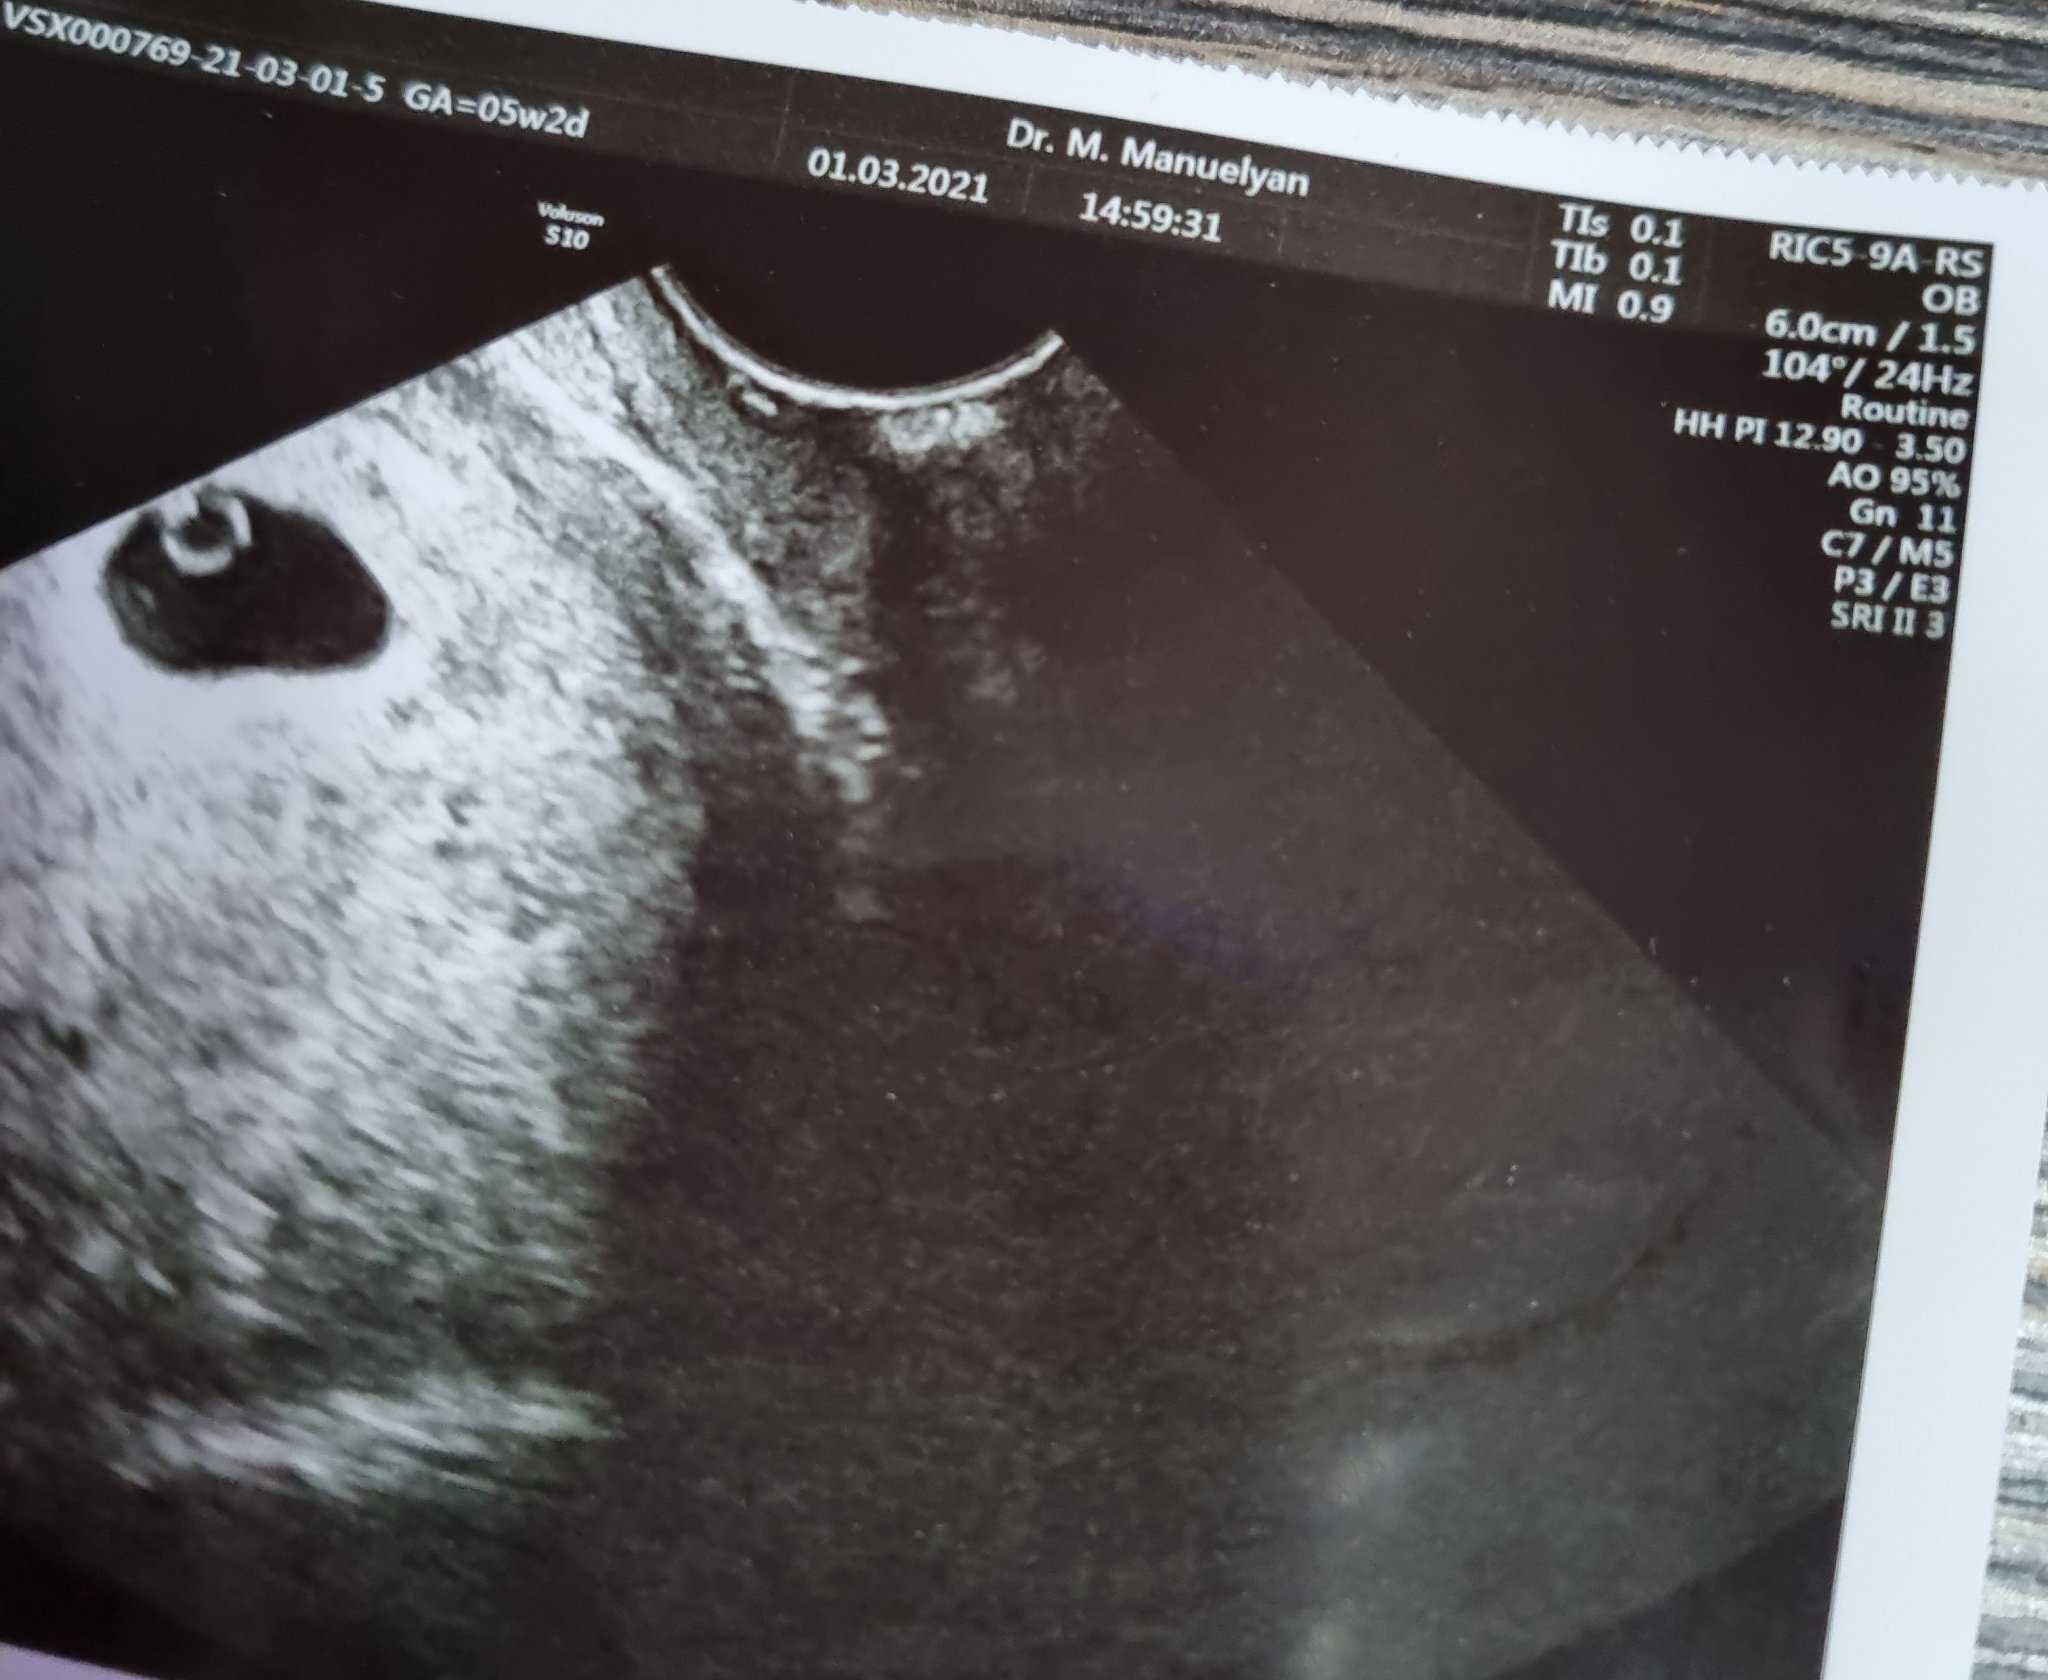

Кървенето по време на бременност може да се прояви с леки коремни болки и различни нюанси на кръвоизливи - блед розови петна върху ежедневната превръзка и тъмно кафеви нишки върху хартията. Това може да е признак за кървене, което обаче може да бъде безвредно. Важно е да се консултирате с лекар, за да сте сигурни в здравето на бебето и да получите необходимите насоки за грижи по време на бременност. Симптомите на ранна бременност могат да включват болезнености в гърдите, гадене, повръщане, повишена чувствителност към миризми, умора, често уриниране, кафяви петна по бельото и коремни и кръстни болки. Всички тези симптоми са обичайни и могат да варират от жена на жена.

При кървене по време на бременност е изключително важно да се консултирате с лекар за оценка на ситуацията. Вашият лекар може да предложи пълна почивка и допълнителни тестове, като например вливания или лекарства за поддържане на бременността. Важно е да следвате инструкциите на вашия лекар и незабавно да се свържете с него, ако имате някакви симптоми или притеснения.